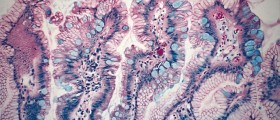

Heartburn can be described as a painful, burning sensation which commonly occurs in the thorax or the throat and is more often than not accompanied by a sour or bitter taste in the mouth. Heartburn may be an indication on gastro esophageal reflux disease which may involve symptoms such as a chronically hoarse voice, weight loss, bouts of asthma and swallowing difficulties. The condition may worsen significantly if neglected and left untreated. The severe form of the condition is sometimes referred to as the Barrett’s esophagus and it may be really dangerous as it may be affiliated with the occurrence of esophagus cancer. A healthy human body contains a muscle which resembles a ring, whose main purpose is to allow the drinks and foods to pass into the stomach. Once it performs it primary function, the muscle contracts in order to shut off any reverse flow of the stomach contents. The muscle can get weaker due to numerous different factors, so the stomach juices get into the esophageal cavity which causes heartburn and certain internal damage. The muscle is medically referred to as the lower esophageal sphincter, and it is actually the valve that prevents that shuts the esophagus off from the stomach. Different factors which may cause this condition may be indirect or direct and they may also be interconnected. Some factors are responsible for the initiation of the problem, while certain others only aggravate the existing situation.

The most common factor is excessive production of gastric acid which is usually caused by certain types of genetic deficiency. This causes the acid to flow back into the esophagus and irritate or damage its inner walls. Candida may also sometime overgrow inside the human body, which often leads to a weakened immune system and the development of more than 70 different types of harmful toxins. These toxins cause numerous medical conditions and the gastro esophageal reflux disease is only one of them. For those who do not know, Candida is a fungal microbe which commonly can be found in the human body and it is completely harmless if present in controlled quantities.